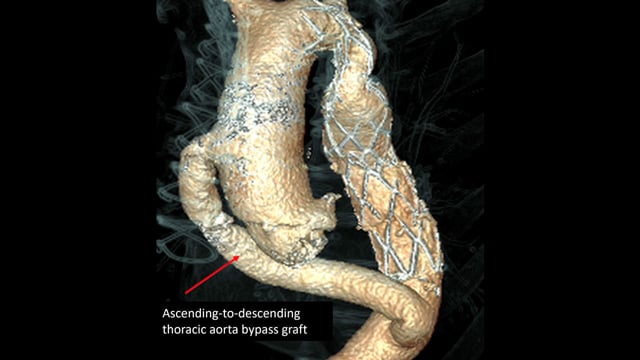

A challenging valve-in-valve scenario in a patient with prior aortic coarctation repair

16 Feb 2026

A 79-year-old with a degenerated aortic bioprosthesis after complex coarctation surgery challenges conventional strategies. Which access route would you choose?